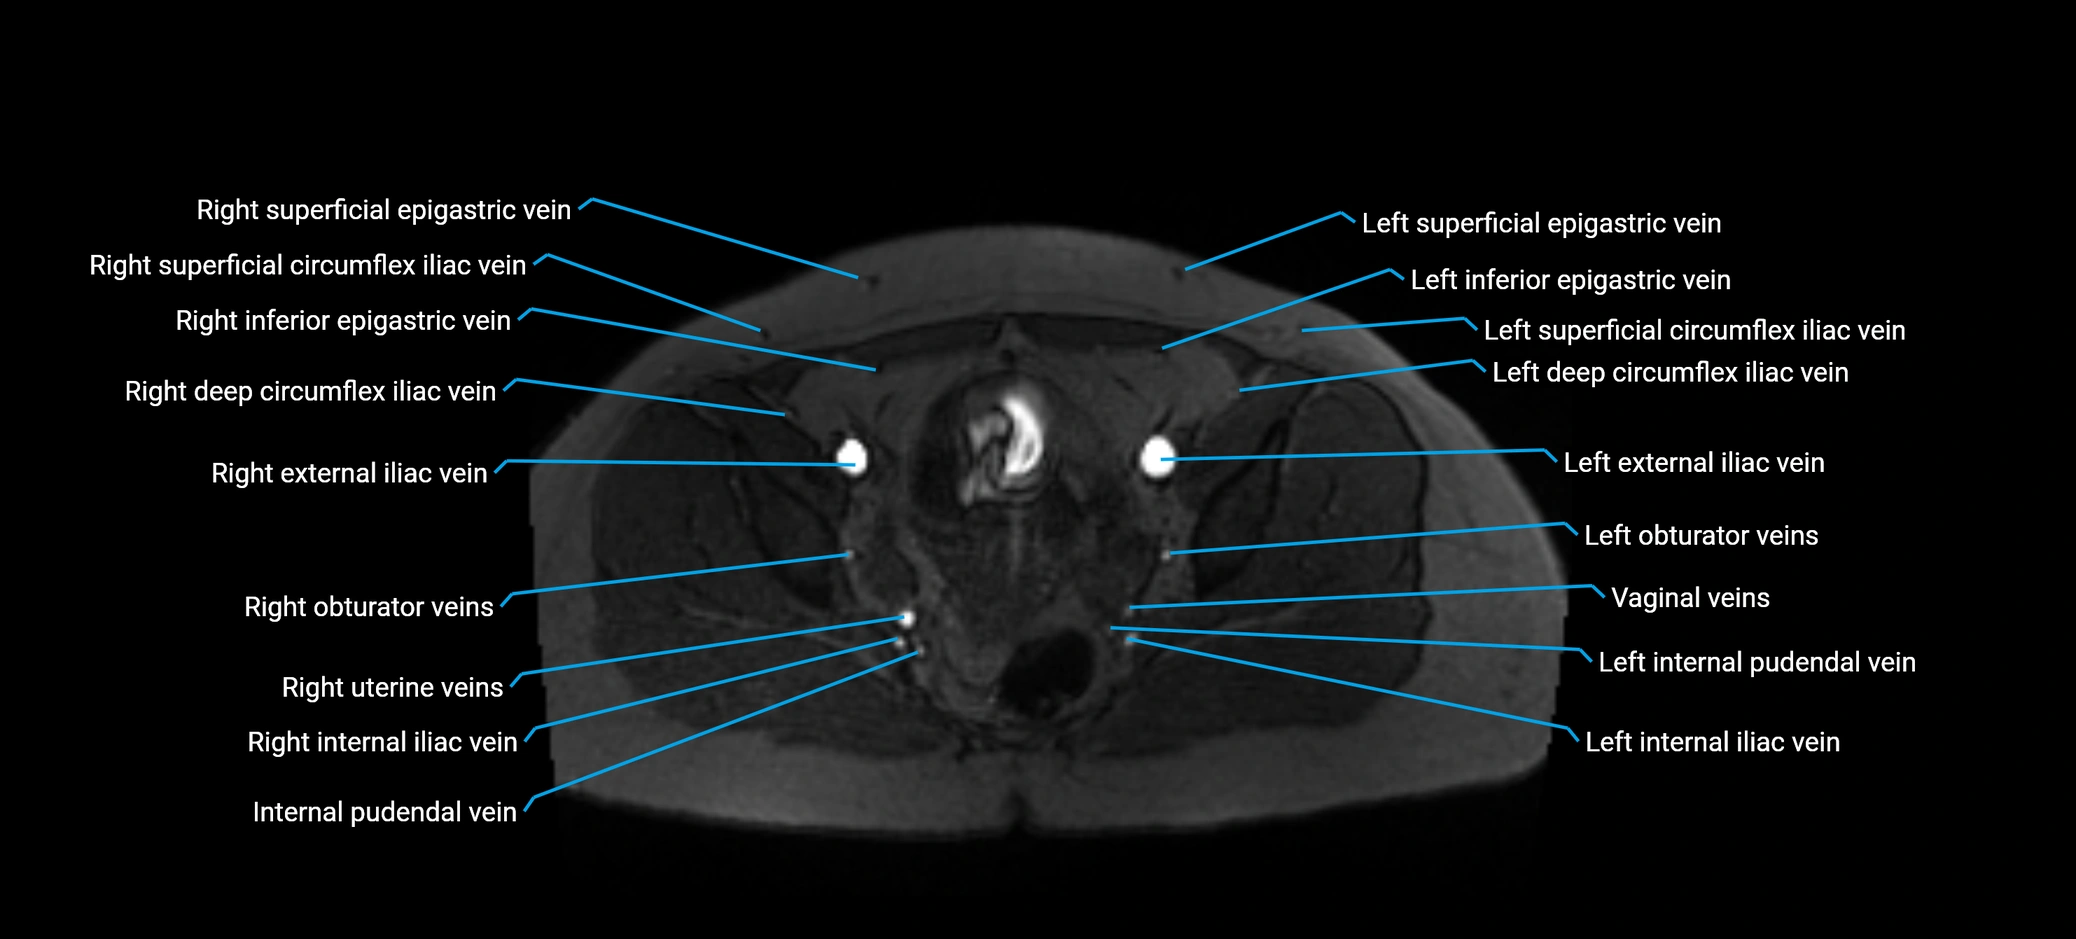

MRI image

image